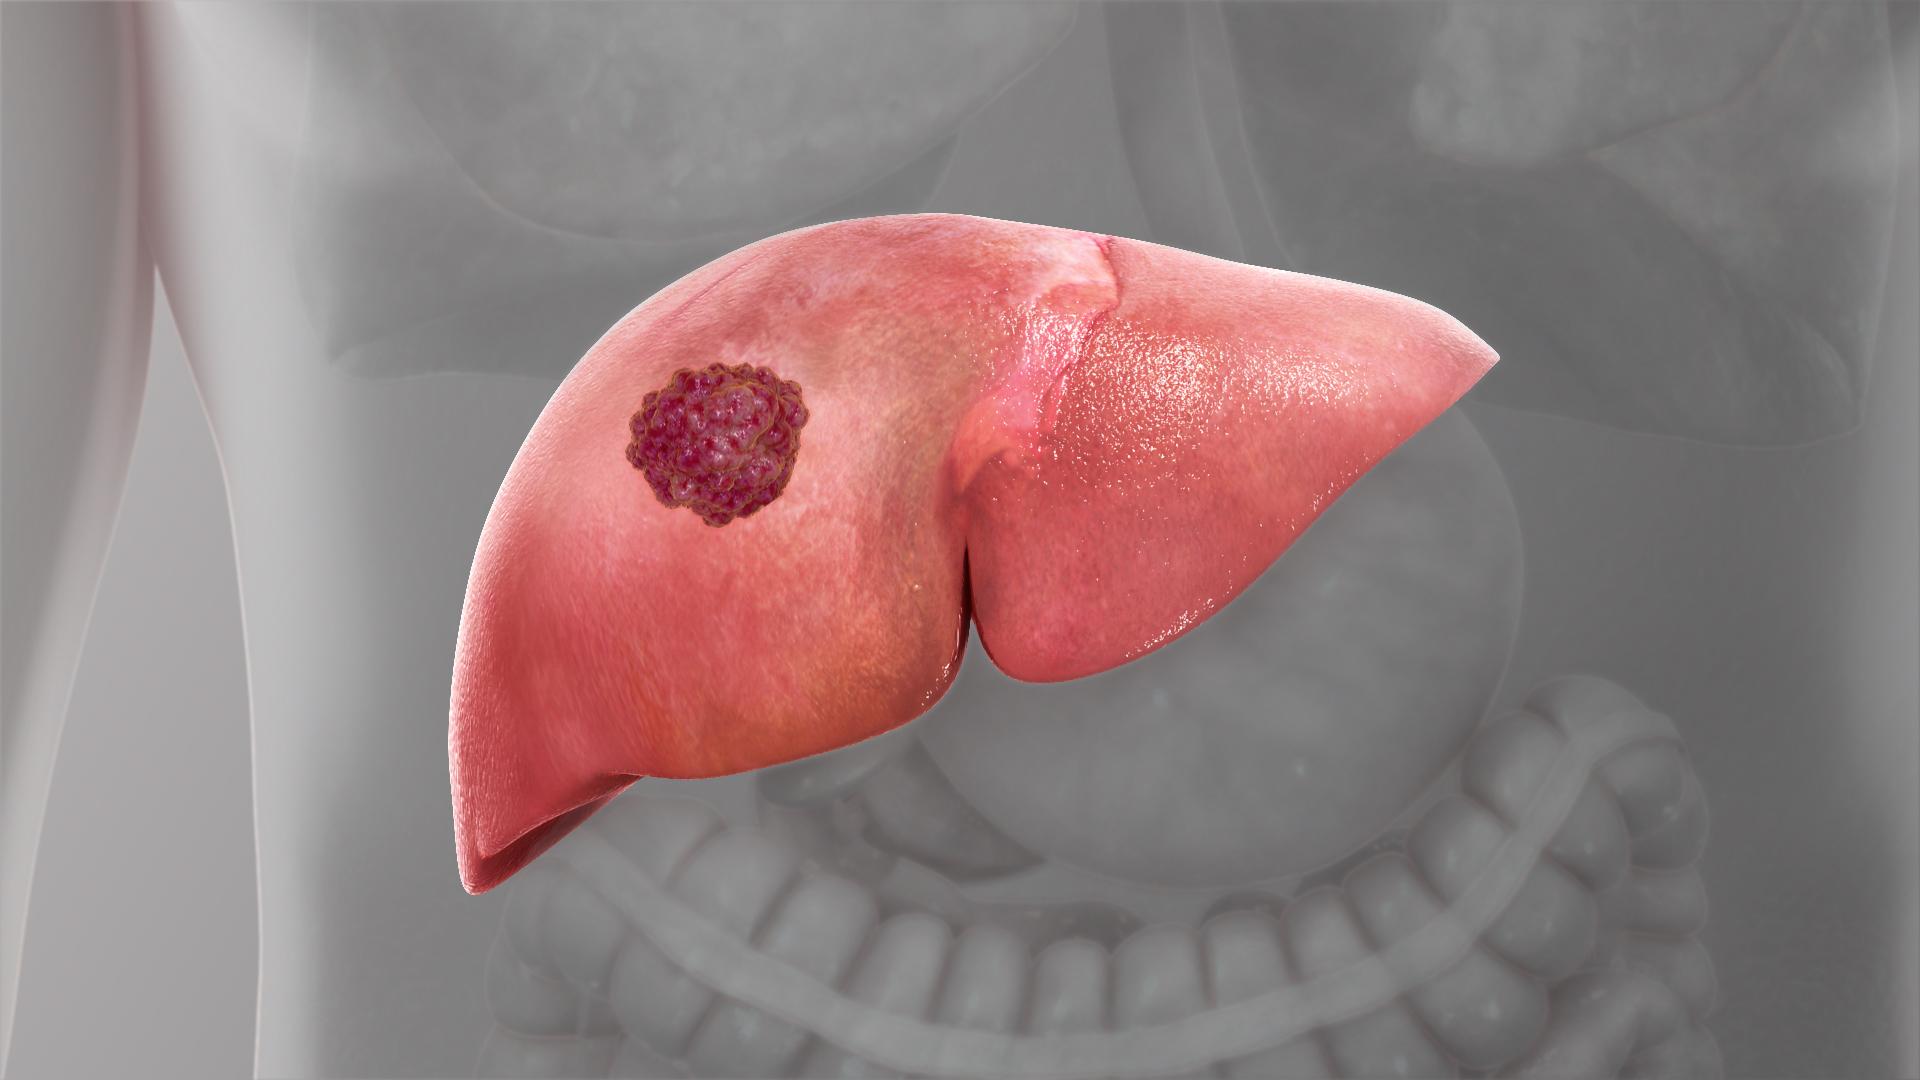

羅東博愛醫院胃腸肝膽科江明峯主任表示,隨醫療與藥物普及,乙型、丙型肝炎威脅降,反之因不良飲食與習慣導致的脂肪肝成最易被忽略的隱形殺手。脂肪肝是近十年來最容易被忽略的肝病,也是新陳代謝症候群的一種,脂肪在肝臟過度的堆積,導致肝臟長期發炎,疾病可能直接進展為肝癌,且初期大多無症狀。

脂肪在肝臟過度的堆積,導致肝臟長期發炎,疾病可能直接進展為肝癌。